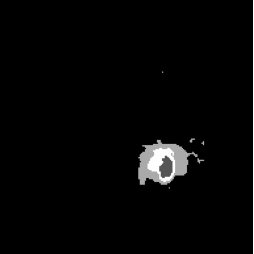

FNO Baseline (Figure 4, PDF page 8)

FNO ground-truth mask.

Ground Truth

FNO prediction mask.

Prediction

DICE 65.13% · Captures global context but loses boundary precision.